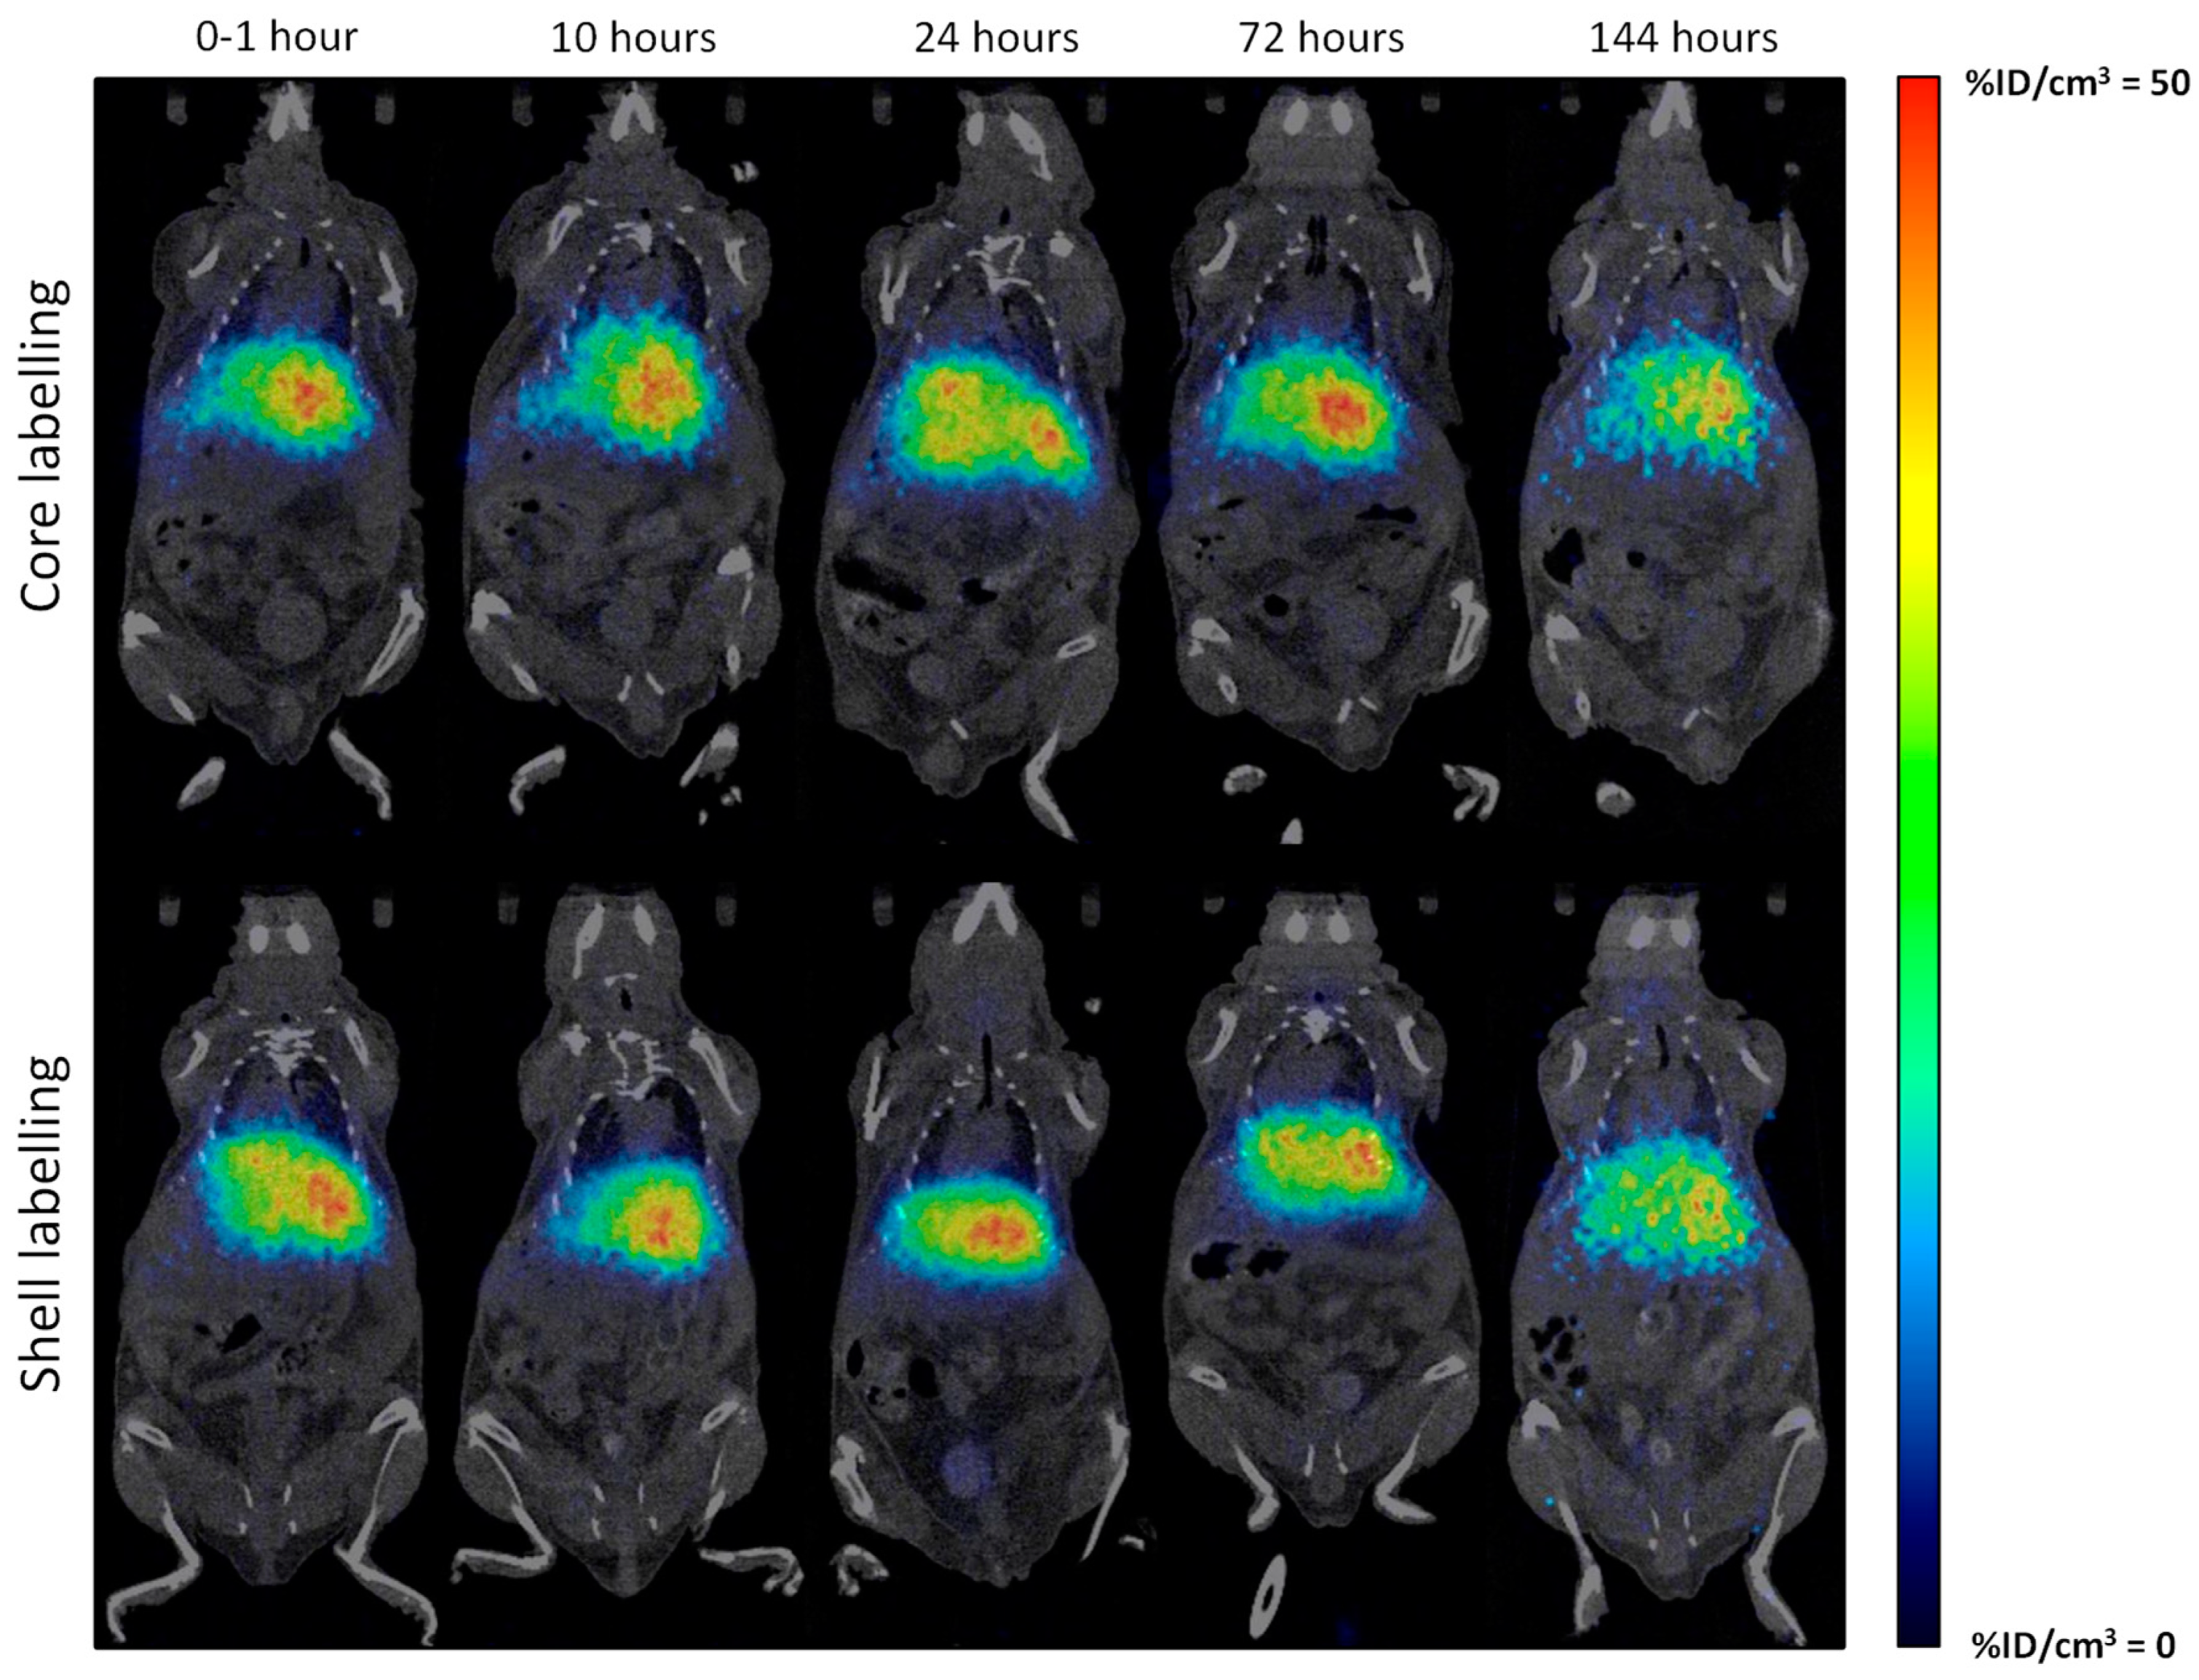

2.4. In Vivo Imaging Studies